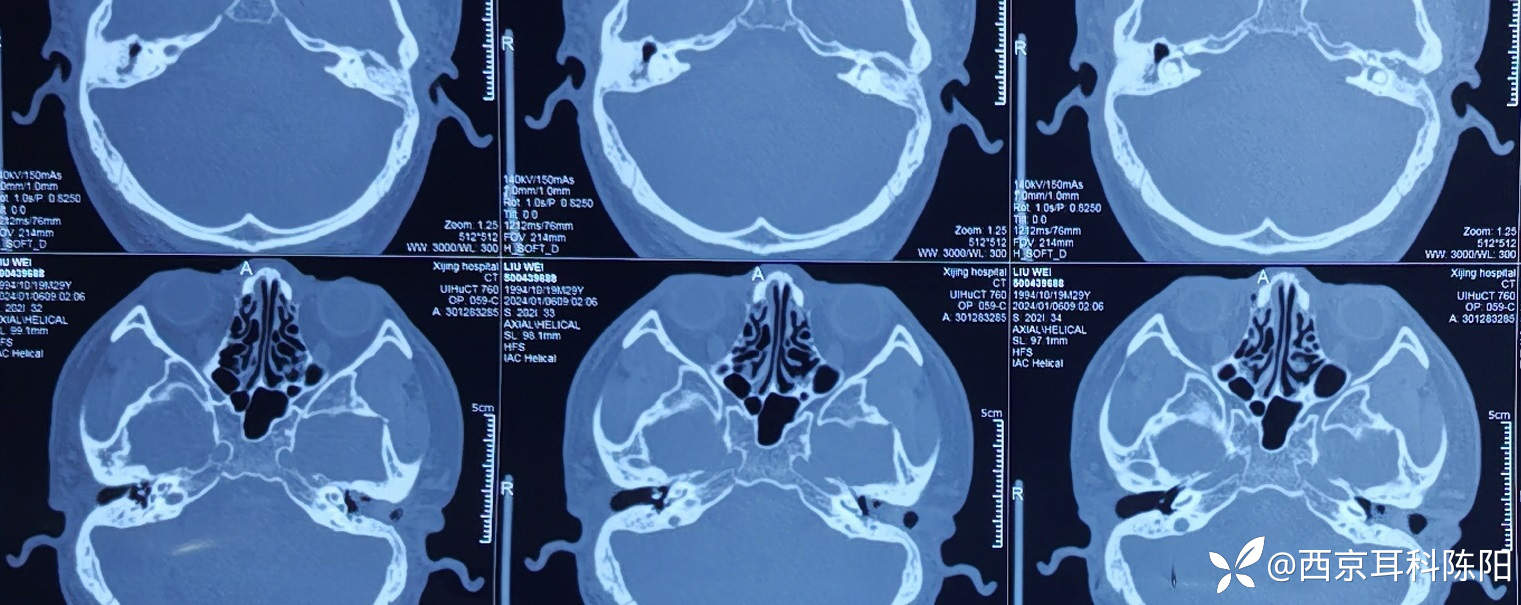

病例2018-11-19的4型鼓室硬化-1期鼓室成形术

钩针清理镫骨和面神经水平段之间的硬化灶后,用自体砧骨塑形桥接镫骨头与锤骨柄